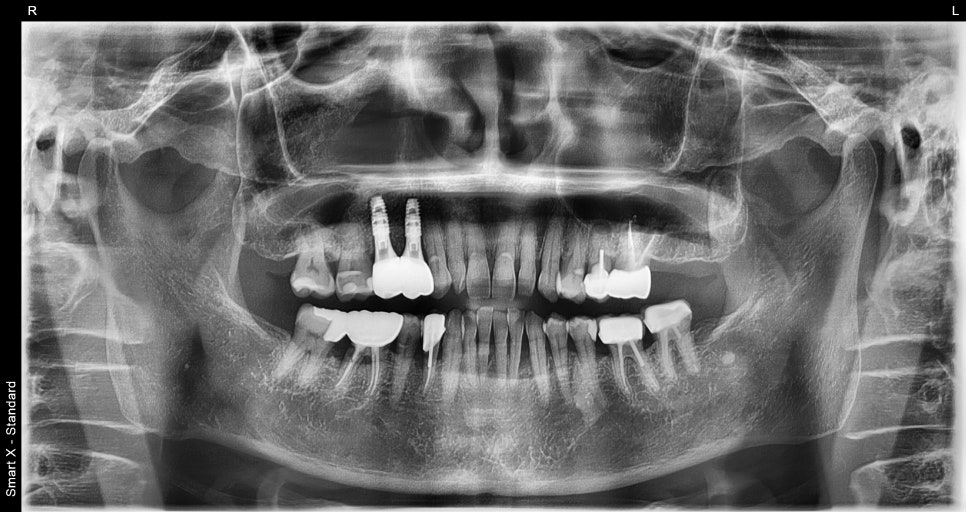

Implant treatment starts with an accurate diagnosis.

At Seoul Oue Dental Hospital, panoramic imaging and

CT scans are used to check the following:

The thickness and height of the jawbone

The location of nerves

Whether there is existing inflammation

The condition of surrounding teeth

The patient in their 60s also learned through these tests

that “the bone needs to be reinforced before placing the implant.”

Previous image

This is because the amount, structure, and gum condition of the bone

are different for each patient.